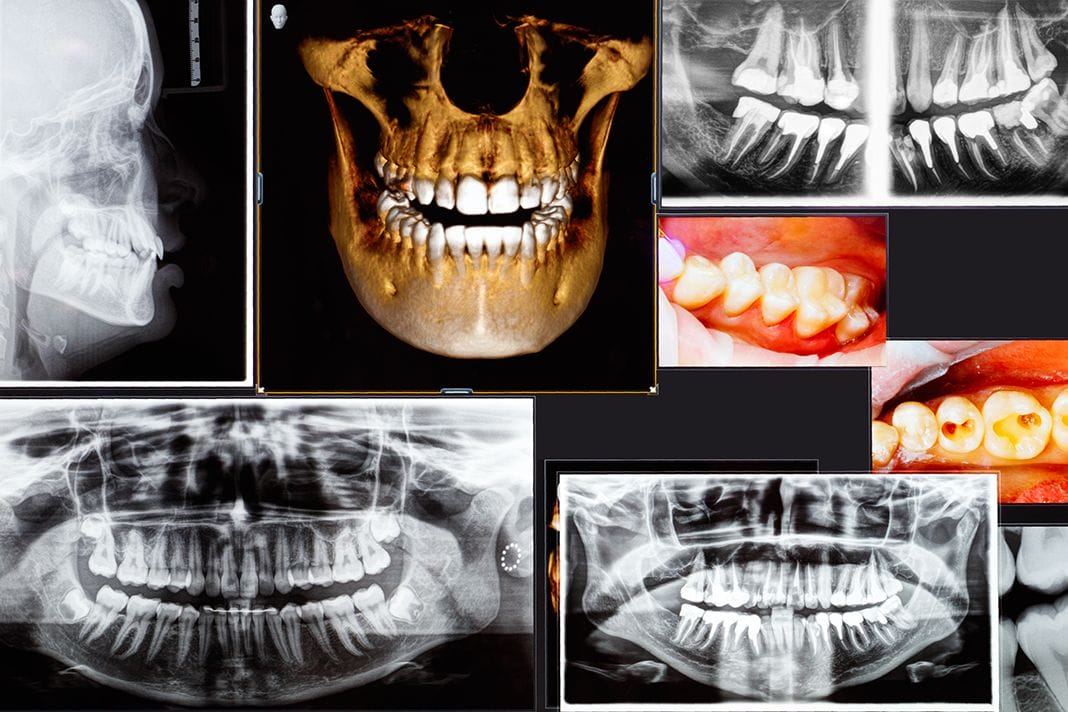

It’s 2018, and to my surprise, there are many dental practices still using film radiographs. Although there is nothing wrong with film radiographs, we can all attest that digital images offer not only lower exposure to radiation but also clearer images versus traditional film. With clearer images, the doctor can make an accurate diagnosis in the treatment planning, and you as the hygienists, can provide the best recommendations to the patient, right? As a hygienist, I did believe my patients were receiving the best recommendations we had to offer until the cone beam computed tomography scan, or CBCTs/CT scan, caused a paradigm shift in how I now approach my patients’ oral health care.

I came across a patient who was experiencing gingival pain in the lower right quadrant. Tooth number 31 was endodontically treated. A 2D digital image was taken, and the doctor found no obvious concerns. The patient was referred to the dental imaging center where I am employed, and we did a 3D cone beam CT scan. The CT results showed bone loss on the mesial wall and through the furcation of tooth number 31.

I also came across multiple referred patients with a history of sinus problems, who presented to our imaging center experiencing a toothache, and the 2D digital image that was taken at their dental home showed no obvious concerns. The 3D cone beam CT scan we took showed a defect in the bone and the infection draining into the sinus like the example pictured here.

Seeing the results of their images made me wonder; is the patient’s sinus infection caused by a nasal infection or a tooth infection draining into the sinus cavity? When a patient presents with a chief complaint regarding their gingiva, I assume a popcorn kernel could be lodged subgingivally or perhaps flossing trauma. Now I’m wondering, could the pain be bone loss occurring that is not yet viewable on a 2D digital image? What about our patients who present to their appointment with no chief complaints and their periodontal assessments and 2D digital images appear fine? Are those patients really within normal limits with no obvious concerns?

These questions I began asking myself created an “ah-ha light bulb” moment for me and WOW, was I excited! I was excited to ask the doctors that do not currently refer out or use a 3D cone beam CT scan on their patients these questions, and I look forward to challenging their thought process. If specialty practices such as Endodontist and Oral Surgeons utilize the 3D cone beam CT for their patients’ treatment planning, why aren’t the General Practitioners considering the use of 3D cone beam CTs for their patients? Whether it’s referring their patients out to an imaging center or purchasing their own, a 3D cone beam CT scan implemented into the practice as the new standard of care benefits the patient and the practice. It creates a true preventative approach for the practice by identifying areas that may need to be addressed before the patient experiences any symptoms. There may be problematic areas other than what is currently treatment planned, or there may be no significant findings and the patient is truly within normal limits.

A cone beam CT scan is not only used to rule out pain of unknown origin or pathology but can also assess their airway for areas of possible airway obstruction. Your patients will leave their appointment appreciating and knowing they are receiving a thorough examination. So, how accurate are diagnoses based off film radiographs or 2D digital images?